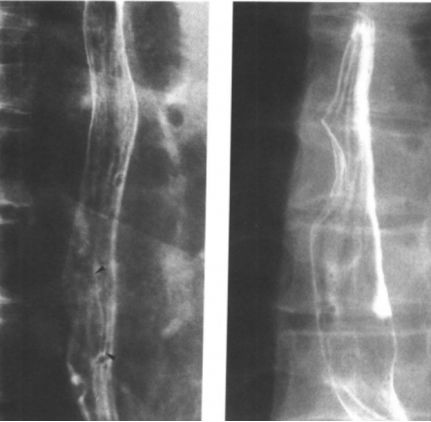

食管静脉曲张:蚯蚓样、串珠状。 医学百科网 | YxBaike.Com

食管重度静脉曲张

食管静脉曲张:食管黏膜呈现蚯蚓状 医学百科网 | YxBaike.Com